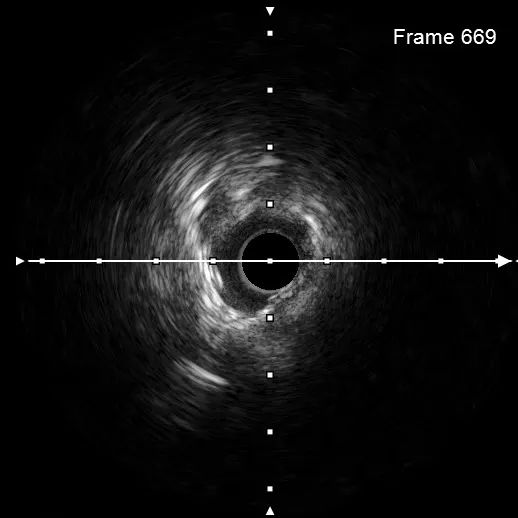

遂采用3.5*12mm Shockwave IVL导管于钙化狭窄处精准治疗。IVL导管充分排气后,送至支架内钙化病变部位,充盈1:1造影剂盐水,并扩张至4atm,按动IVL连接手柄按键,一键启动血管内冲击波发放,每秒1次脉冲,每10个脉冲为一组;每组血管内冲击波治疗后,回抱IVL球囊,以充分排出“震波”剩余气泡,避免能量损失。再将导管扩张至4atm。进行下一组血管内冲击波治疗。过程中,可见IVL球囊充盈缺损逐渐消失,直观展现了斑块重塑、血管松解。

最终,共进行3次血管内冲击波治疗后,复查原支架膨胀不良处可见膨胀改善。